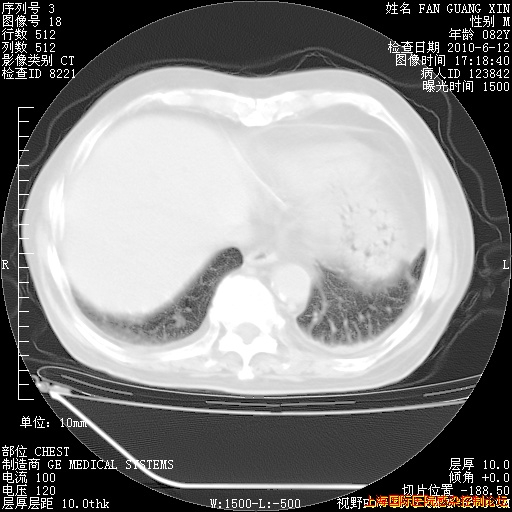

6月12日肺窗

整整相隔30天的肺部CT好像有所好转啊。甲强龙减量第3天,需要观察体温。